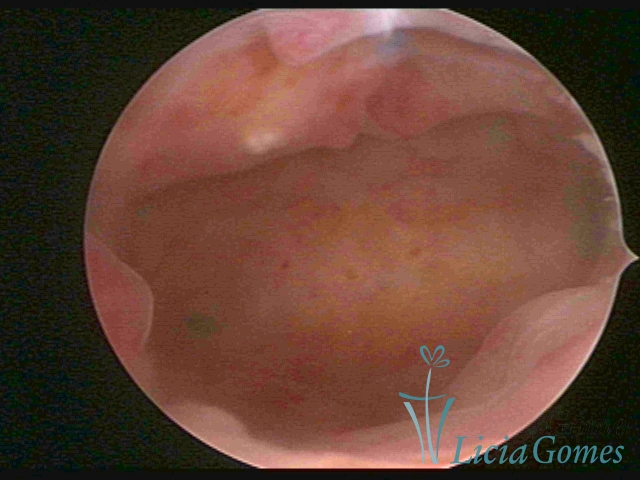

Na hipertrofia simples há um aumento da espessura endometrial com protuberância do pontilhado glandular, diferindo do padrão endometrial proliferativo pela perda da vascularização reticular superficial. Outra forma de hiperplasia simples é a glandular cística, onde também se visualiza lesões císticas intercaladas ao endométrio hipertrófico.